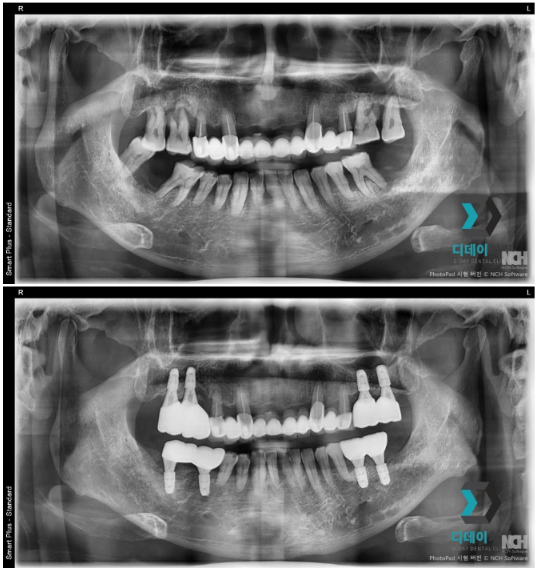

양쪽 위아래 어금니 치주염으로 내원하신 환자분입니다.

양쪽 어금니 심한 치주염으로 인해 발치 후

즉시 임플란트 식립을 진행했습니다.